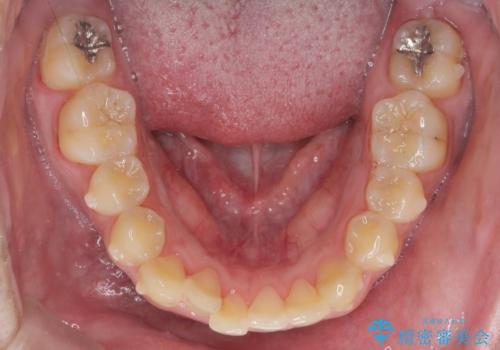

正中過剰埋伏歯で生じた前歯の審美障害 矯正治療での改善

見た目、噛み合わせが大きく改善し、大変喜んでいただくことができました。